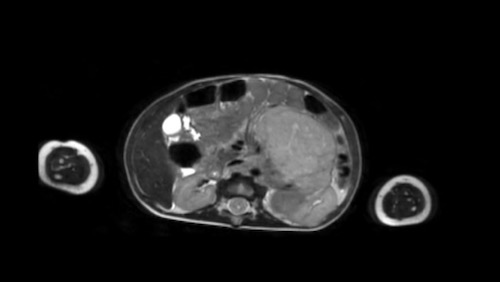

Siêu âm của một bé trai mười lăm tháng tuổi, ban đầu được nghi ngờ có khối u ở thận trái.

Siêu âm cho thấy một khối u nằm kề cực trên phía trong của thận trái. Khối u có vẻ tách biệt với thận. Khối u rất không đồng nhất và có nhiều vôi hóa.

Những phát hiện này phù hợp với u nguyên bào thần kinh hơn là u nguyên bào thận.